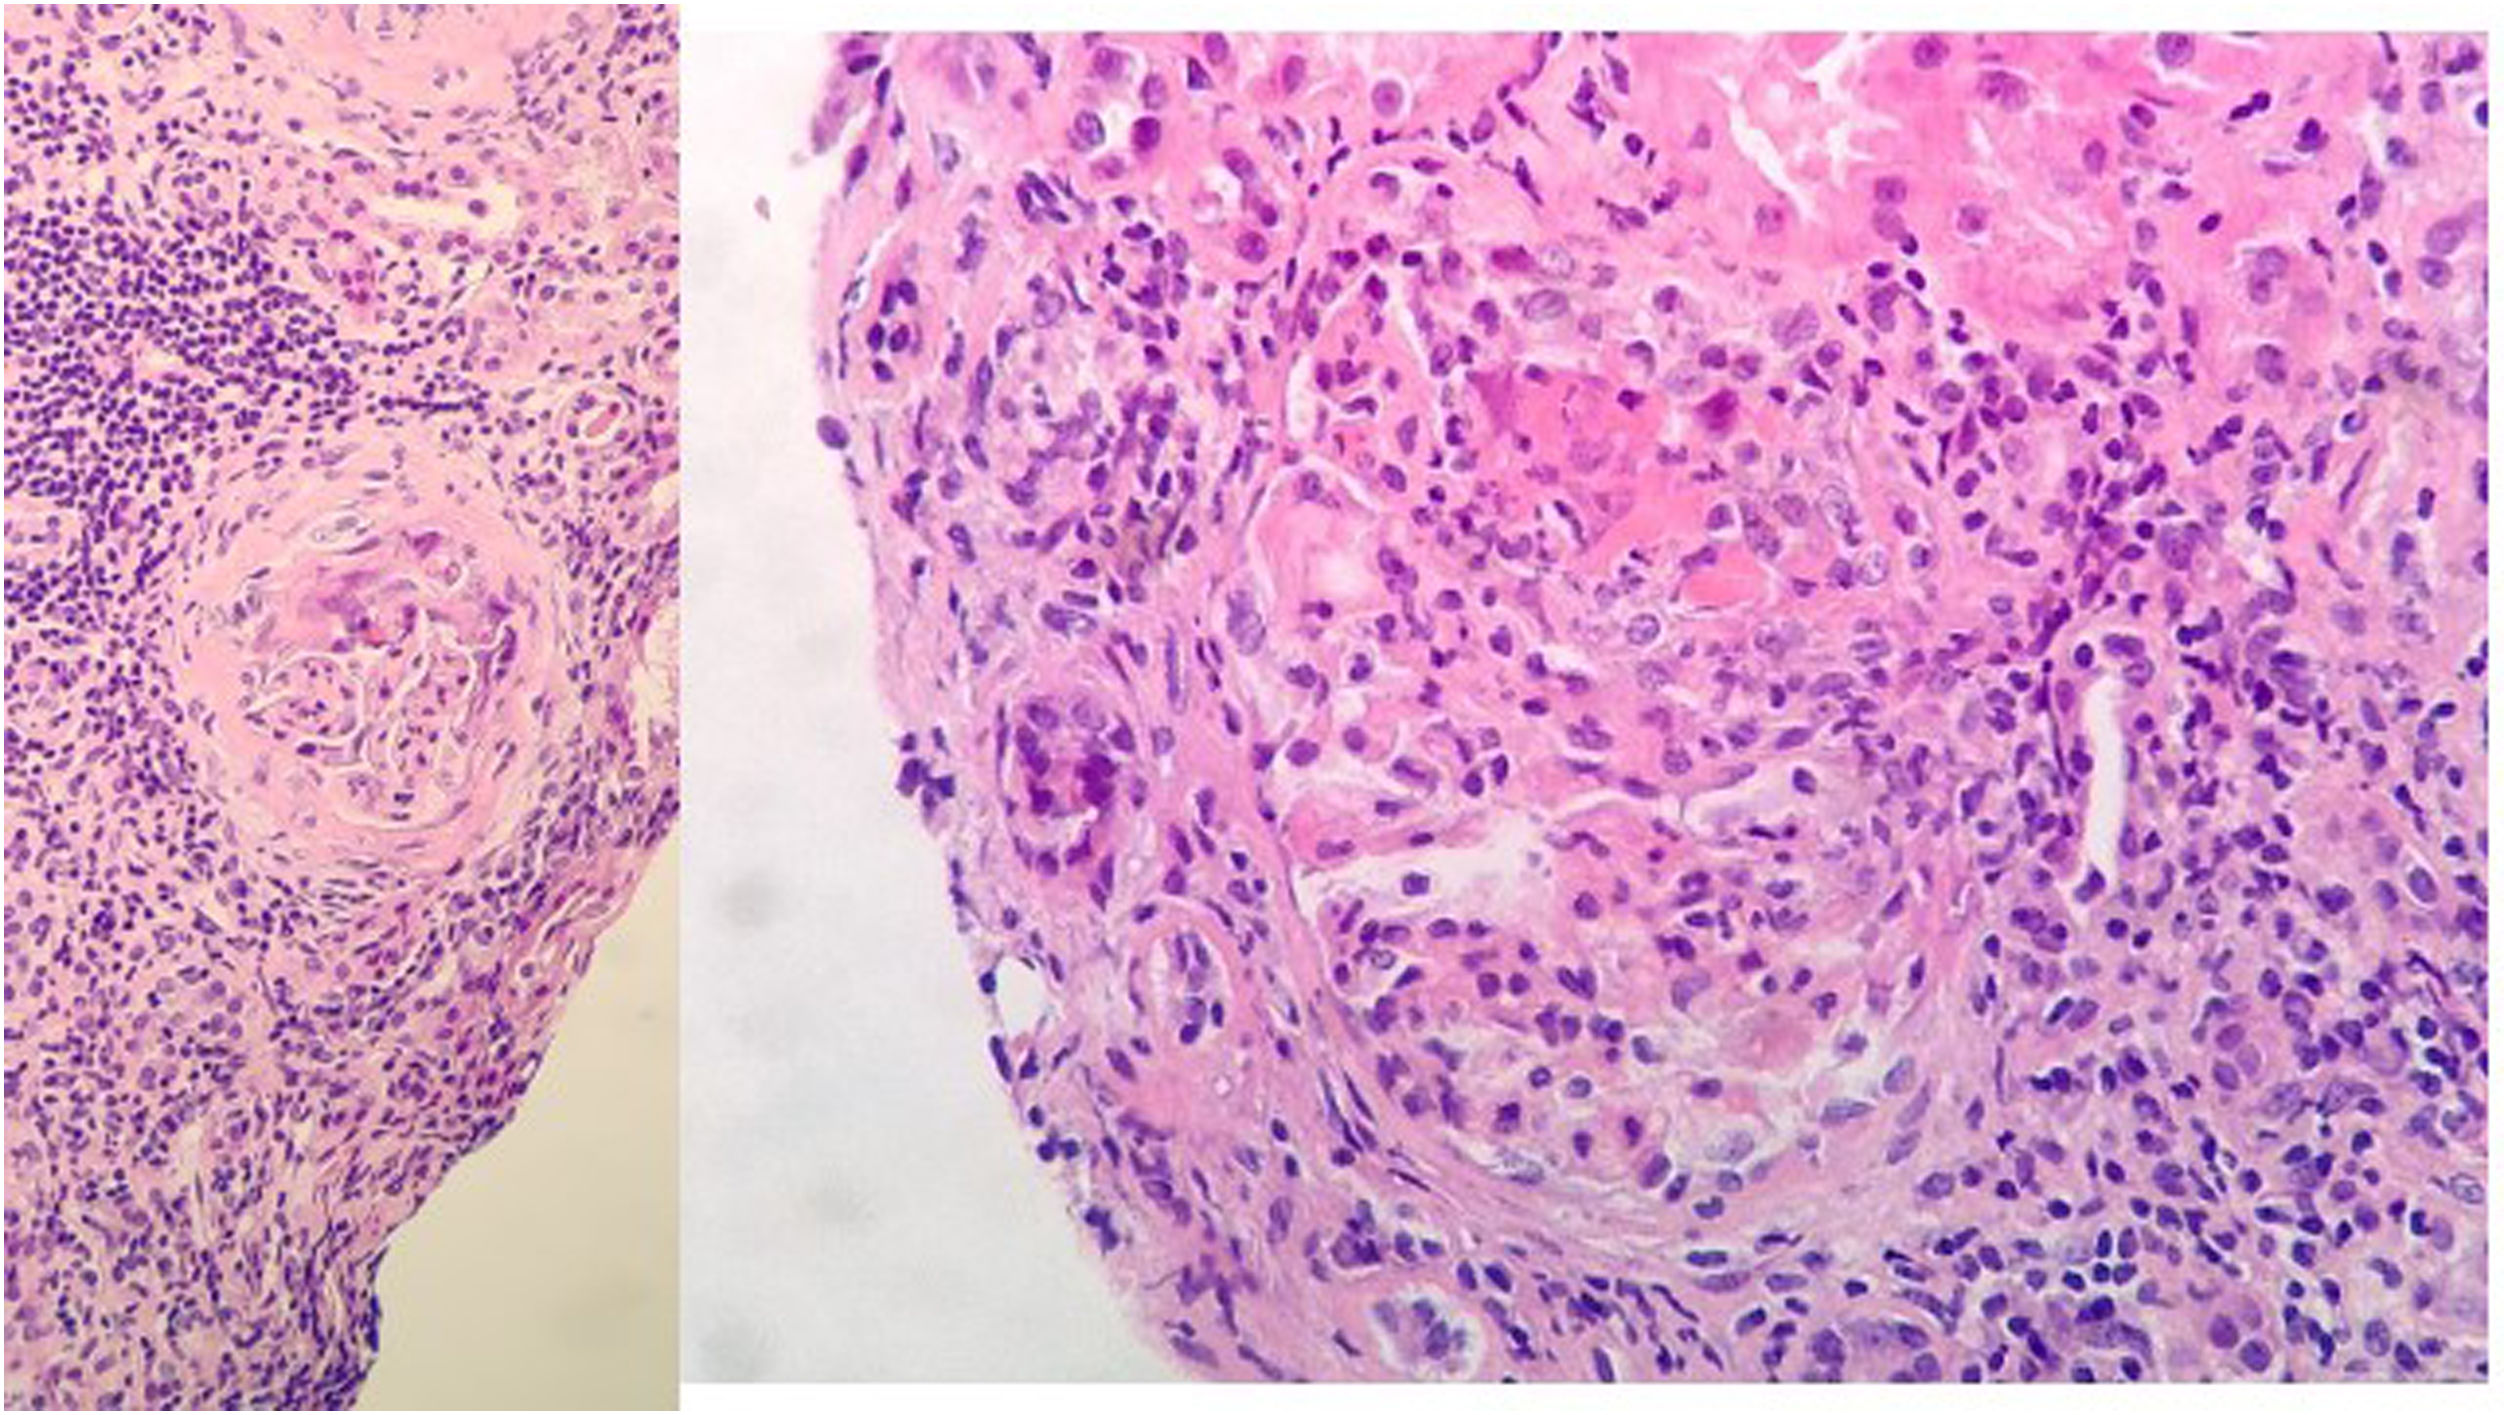

Evolución y pruebas complementariasA su ingreso, inicia tratamiento con levofloxacino, anticoagulación profiláctica con HBPM y soporte respiratorio. Evoluciona a mayor insuficiencia renal y respiratoria. Se realiza biopsia renal a los 10 días de ingreso, con juicio clínico de glomerulonefritis proliferativa extracapilar de tipo mixto pauciinmune asociada a ANCA con cambios crónicos moderados (imagen 2).

Biopsia renal: 11 glomérulos, 3 globalmente esclerosados. Cinco con cambios congestivos menores y 3 con proliferación extracapilar y formación de semilunas celulares Compartimento túbulointersticial con inflamación crónica y aguda, atrofia tubular del 30%, tiroidización tubular y fibrosis del intersticio del 30%. No cambios en vasos de mediano calibre, ni engrosamiento de la media arterial. No depósitos congófilos. Inmunofluorescencia directa con leve depósito mesangial granular de C3+, sin depósitos de IgG, IgM, IgA ni restricción de cadenas ligeras.